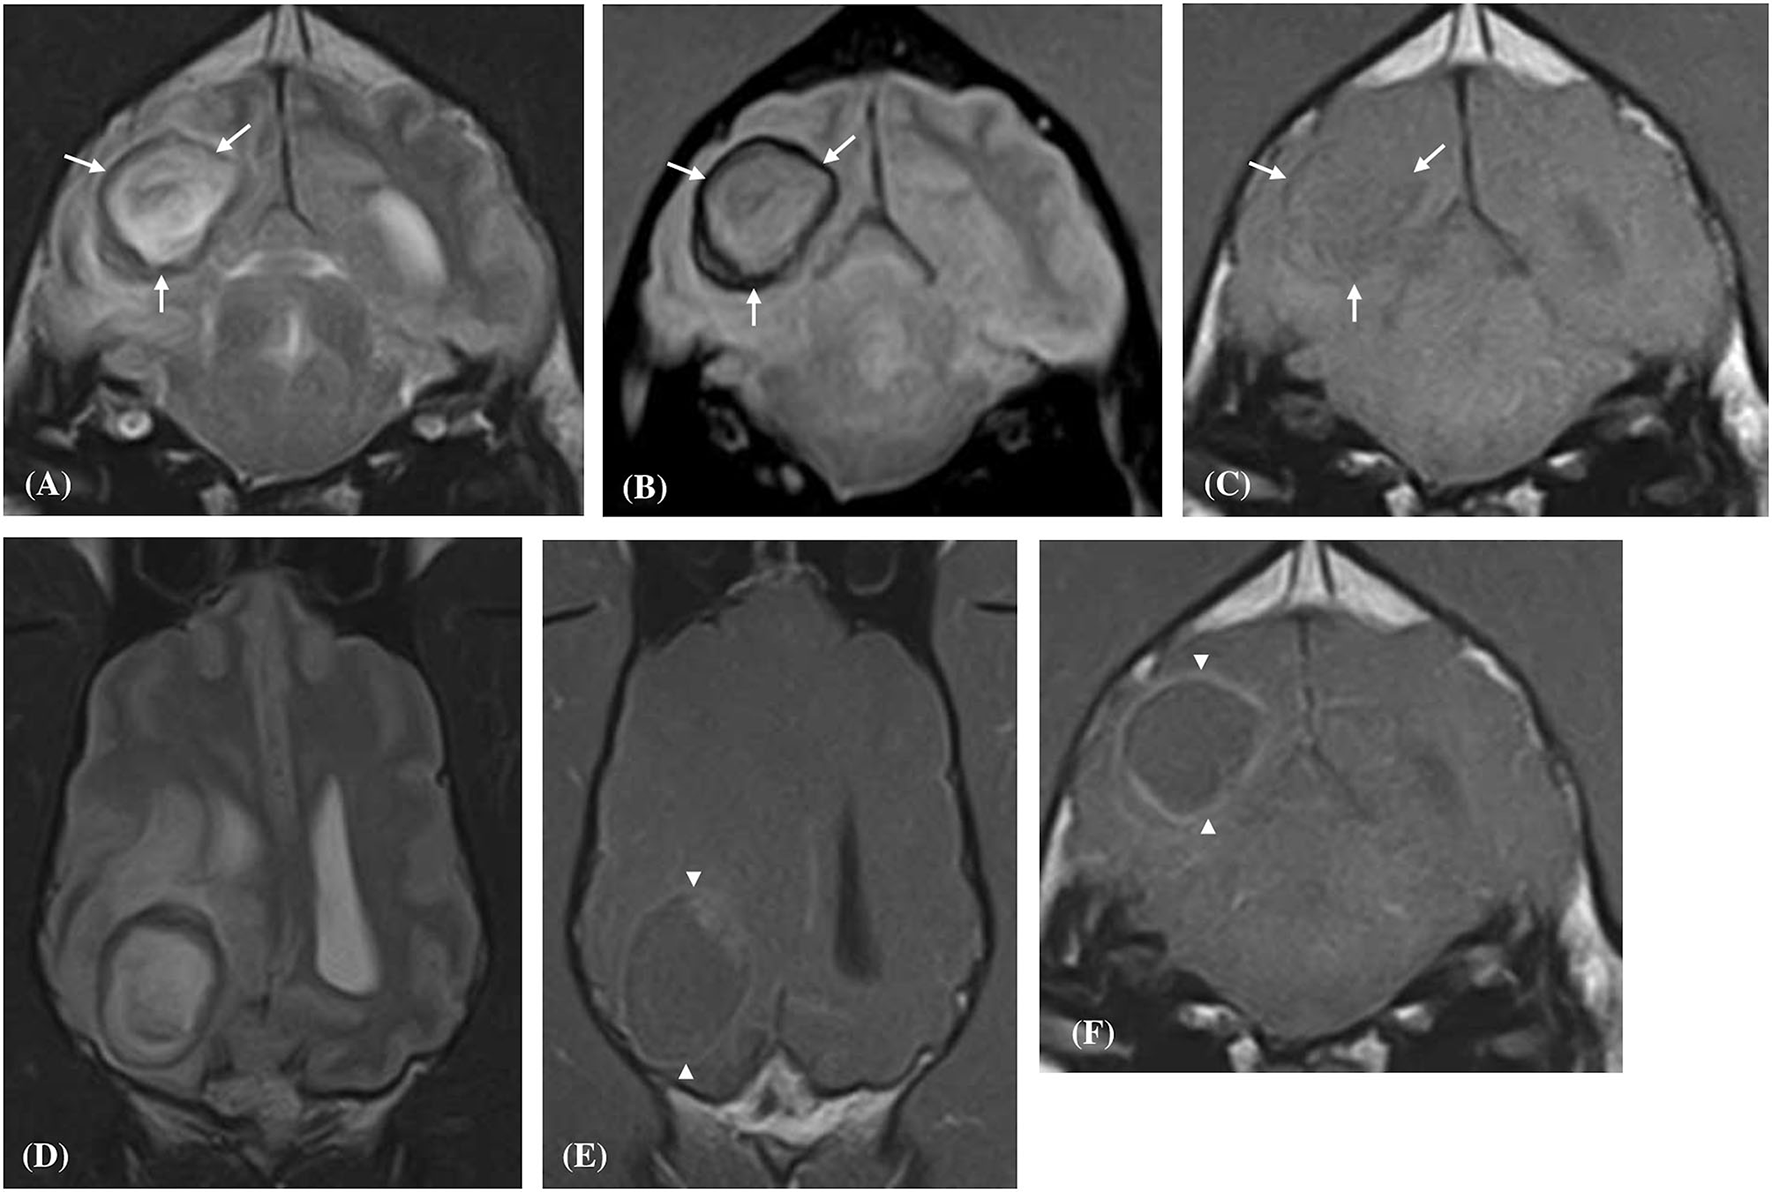

Figure 2

Transverse (A–C,F) and Dorsal (D,E) magnetic resonance images of a dog (Case 6) with a solitary well-defined intracranial intra-axial hematoma affecting the white matter of the right occipital lobe and associated perilesional oedema. The lesion displays a clear regional dichotomy with a hypointense thin, complete, circumferential peripheral border region (white arrows) and a large central predominately hyperintense region (relative to gray matter) on T2-weighted (A,D), T2* gradient-echo (B) images. On pre-contrast T1-weighted images the peripheral border region is again hypointense (C) but is thinner relative to the T2-weighted images. Following contrast administration, the hematoma displays a thin peripheral enhancement pattern (white arrow heads) with no enhancement of the central portions of the lesion (E,F).

Contrast enhancement was evident in (6/10) hematomas and absent in (4/10) cases. When present the enhancement was always present at the periphery of the hematoma (Figures 2, 4). Enhancement was deemed obvious in (4/6) and faint in (2/6) cases. There were no regions of central enhancement within any of the hematoma lesions. Perilesional oedema was classified as moderate in (6/10) and mild in (4/6) hematomas. A mass effect was associated with all hematoma lesions. The mass effect was deemed moderate in (6/10), mild (3/10) and marked in (1/10) of the hematoma cases. A lateral shift of the falx cerebri was noted in (7/10) cases, compression of the lateral ventricles in (4/10) cases, and caudal transtentorial herniation was observed in a single case.